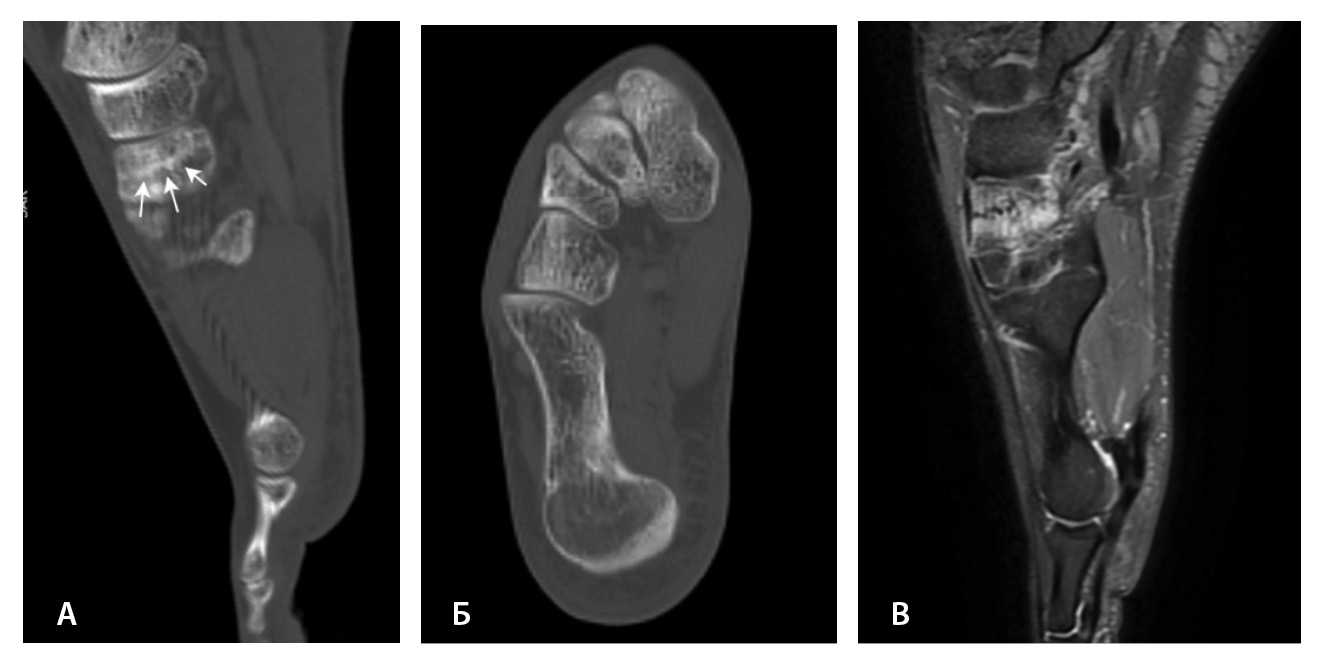

Переломы без смещения фрагментов, а также краевые и авульсионные переломы не всегда четко визуализируются на рентгенограммах из-за суперпозиции теней, наличия фиксирующих шин и гипсовых повязок, которые накладываются на зону интереса. При клинических признаках перелома и рентгеннегативной картине у таких пациентов КТ имеет большую диагностическую значимость (рис. 2).

Рис. 2. Рентгеннегативный перелом дистального метадиафиза большеберцовой кости 2-го типа по Солтеру – Харрису (стрелки) у мальчика 11 лет: А, Б – рентгенография; В – компьютерная томография (КТ), корональная плоскость; Г – КТ, сагиттальная плоскость; Д – КТ, аксиальная плоскость